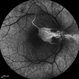

- central retinal artery occlusion (CRAO)

- TOPCON TRX

- This fundus photograph demonstrates the classic retinal whitening due to inner retinal ischemia, with a cherry-red spot at the fovea. The fovea appears red because it is nourished by the intact choroidal circulation, while the surrounding ischemic retina turns pale.